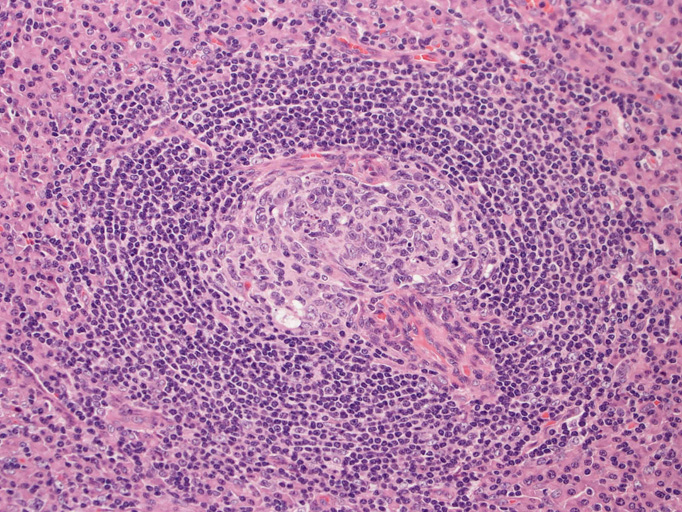

1. 萎縮した胚中心をもつ異常な血管増生を示すリンパ濾胞(Lolli-pop follicles. Lolli-popはキャンディ-の名前のようです)

- 濾胞は小型で周囲を広いmantle zoneで囲まれている。同心円状のよく発達したmantle zoneは「onion skin」と呼ばれる。濾胞は濾胞樹状細胞と進入血管の内皮から構成されている。ときに大型奇異,「異形」細胞が見られるが異常な濾胞樹状細胞と考えられる。-> Dr. Castlemanが「Hodgkin diseaseとの鑑別が必要」といった症例がこのような例に相当すると考えられる(Dr.小島)

- 濾胞内に複数の胚中心が出現することがある。[ one germinal center within a single mantle; twinningと呼ぶ] Frizzela

- 濾胞間組織には非常に多くの細血管が増生する。平坦な内皮やHEVに似た内皮が出現する。細血管周囲に強い硝子化が見られることがある.

「広いmantle zoneの取り巻いたリンパ球の少ないFDCのめだつ小さな濾胞, 硝子化することもある, 濾胞間は細血管でいっぱい」がkey word